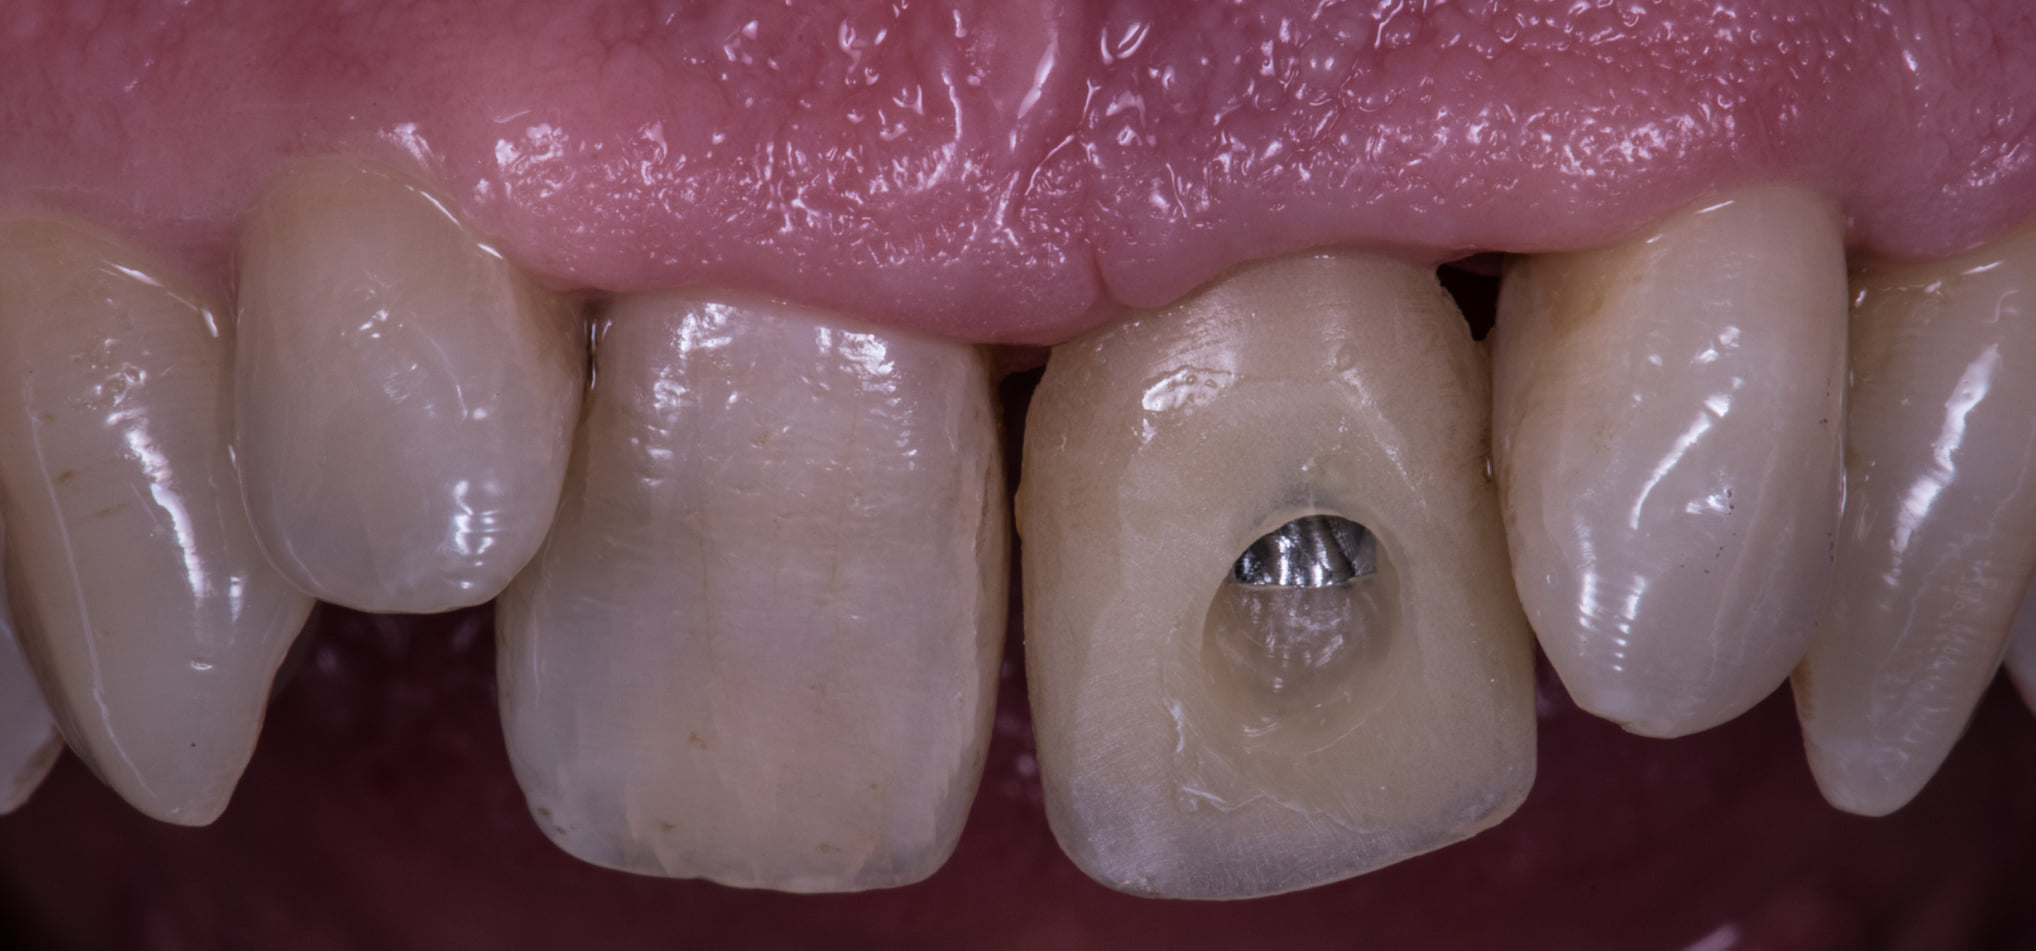

Ieri ho postato alcune foto di una corona avvitata su impianto su un incisivo centrale.

Come spesso accade nei casi frontale mascellari, l’asse dell’impianti era forzatamente inclinato verso palatale quindi il foro di emergenza della vite passante era parecchio vestibolare.

Lo puoi vedere nella foto del provvisorio